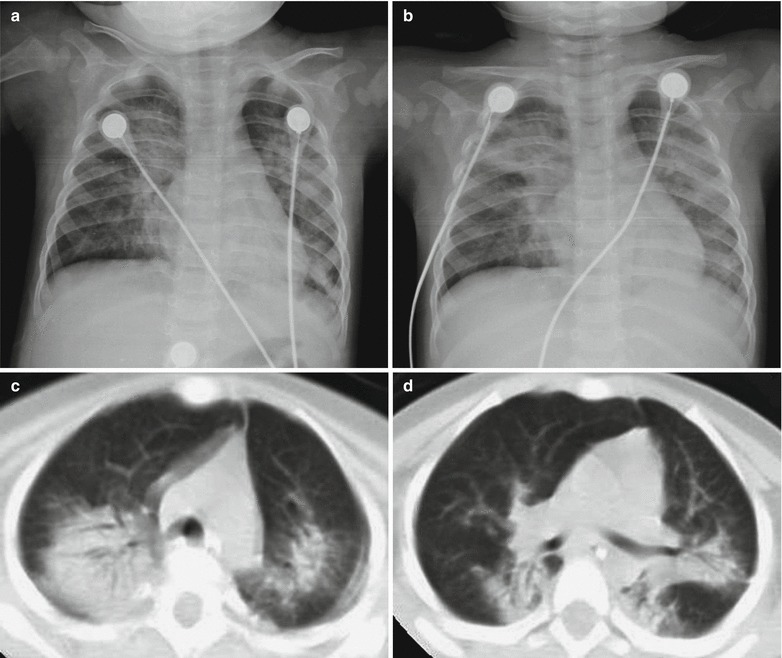

MR Imaging

MR imaging demonstrates no abnormality at the early stage. However, several weeks later, MR imaging demonstrates mild atrophy of the cerebral cortex, hydrocephalus, and demyelination. The lesions are more commonly found at the white matters around the cerebral ventricles, the basal ganglia, the hippocampus, as well as subcortical and cerebellar white matters, with spots or flakes of long T1 long T2 signal and high FLAIR signal. The lesions are more favorably demonstrated by T2WI. DWI demonstrates limited perfusion. Enhanced imaging demonstrates enhancement of some lesions (Fig. 23.2).

Fig. 23.2.

Acute optic nerve encephalomyelitis. (a) Transverse MR imaging demonstrates multiple spots of long T2 signal at the brainstem. (b) Thickened bilateral optic nerves are demonstrated, with uneven enhancement. (c–f) Sagittal imaging demonstrates swelling of spinal cord at the level of C2–T11, with stripes of long T2 signal in the spinal cord. (g, h) Transverse imaging demonstrates long T2 signal in the spinal cord

In patients with spinal cord-related symptoms, MR imaging demonstrates spinal lesions in 80 % of the patients, which are focal or segmental. However, most cases are demonstrated with lesions in long spinal segment (above 3 vertebrae) or whole spinal cord.

The cases of measles complicated by optic neuritis are occasionally reported, with no specificity. Coronal T2WI demonstrates long T2 signal from the optic nerves. Contrast imaging demonstrates enhancement of the lesions, which is more commonly found at unilateral optic nerve.

Immunosuppressive Measles Encephalitis

CT Scanning

CT scanning demonstrates multiple patches of low density shadows at the basal ganglia and interface between gray and white matters. Contrast scanning demonstrates no or slight abnormal enhancement. CT scanning demonstrates apparent atrophy of the cortex or even the brain in the advanced stage.

T2WI and FLAIR demonstrate multiple flakes of high signals with poorly defined boundaries. The lesions might involve the thalamus, basal ganglia, bilateral semiovale centrum, interface between gray and white matters, cerebellum, brainstem, and spinal cord. Contrast imaging demonstrates enhancement of cerebral lesions in rare cases and asymmetric lesions at the bilateral brains. The spinal cord can be demonstrated as stripes of long T2 abnormal signal in segmental spinal cord. Contrast imaging demonstrates slight abnormal enhancement.